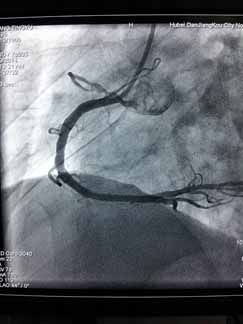

近日,烈日炎炎,急性心肌梗死高发,周六周日两天“120”急救车连续接诊两位急性心梗患者,到达我院后,心血管内科立即开通心梗绿色通道,最短时间内对两例病人实施急诊PCI,配合药物、抽吸导管及冠脉支架治疗,手术进行的非常顺利。门球时间均在60分钟内,堵塞血管立即开通,置入心脏支架,病人获得了最大收益,避免了急性心梗的高死亡率及不良后遗症。